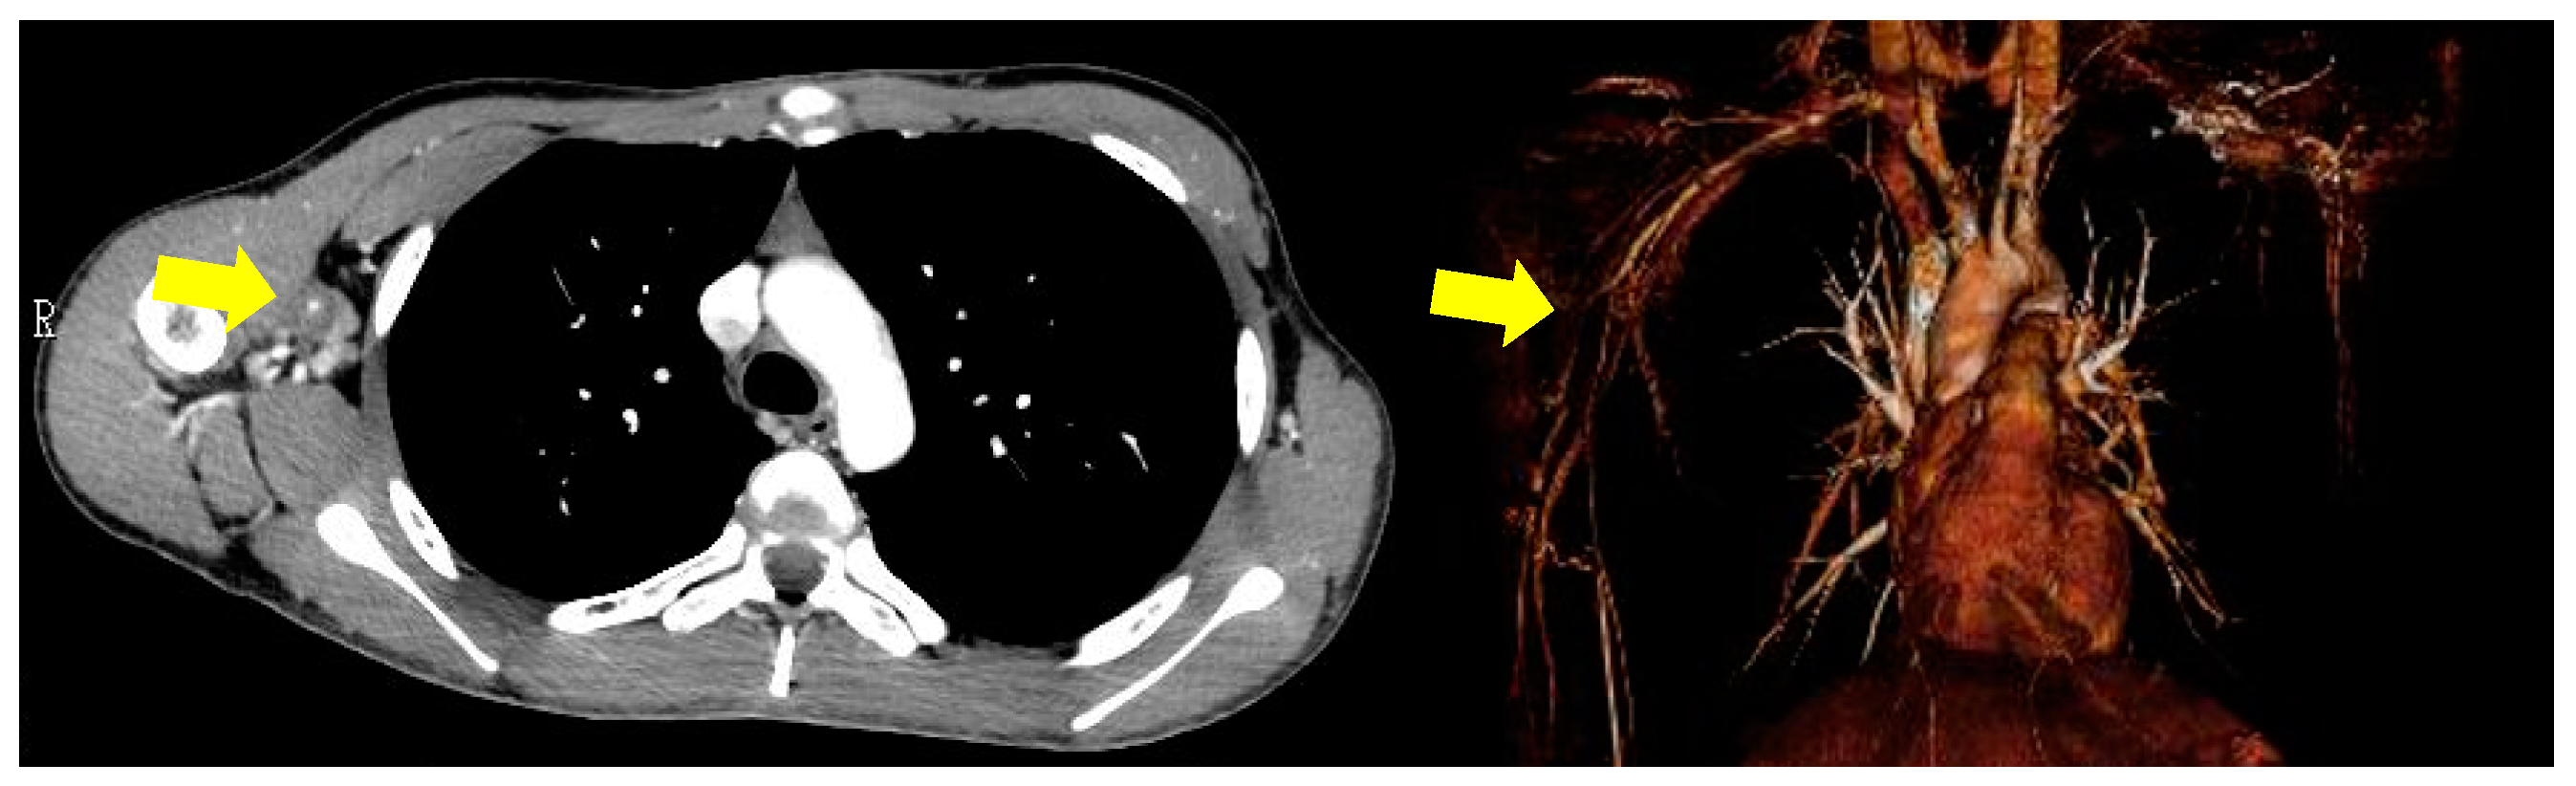

2. Case Presentation